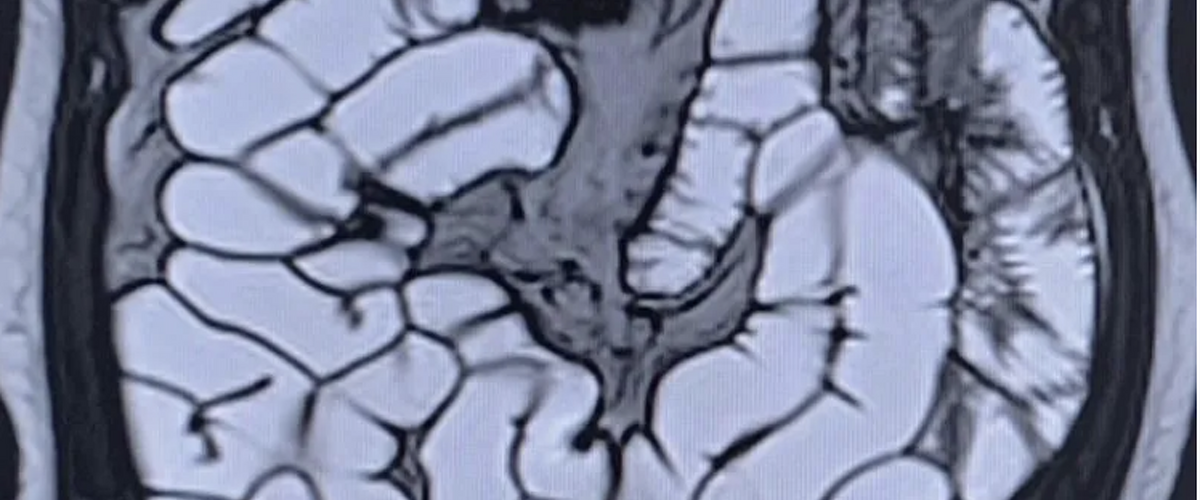

MRI and intestinal ultrasound are increasingly used for whole-bowel assessment, but cine loops and dynamic scans can be time-consuming to review and difficult to standardise.

Multiple peer-reviewed studies show that small bowel motility measured with GIQuant correlates with inflammation and treatment response in Crohn’s disease.

GIQuant has been adopted as an imaging endpoint in multi-centre Crohn’s disease trials, supporting objective and reproducible outcome measures for regulatory submission.